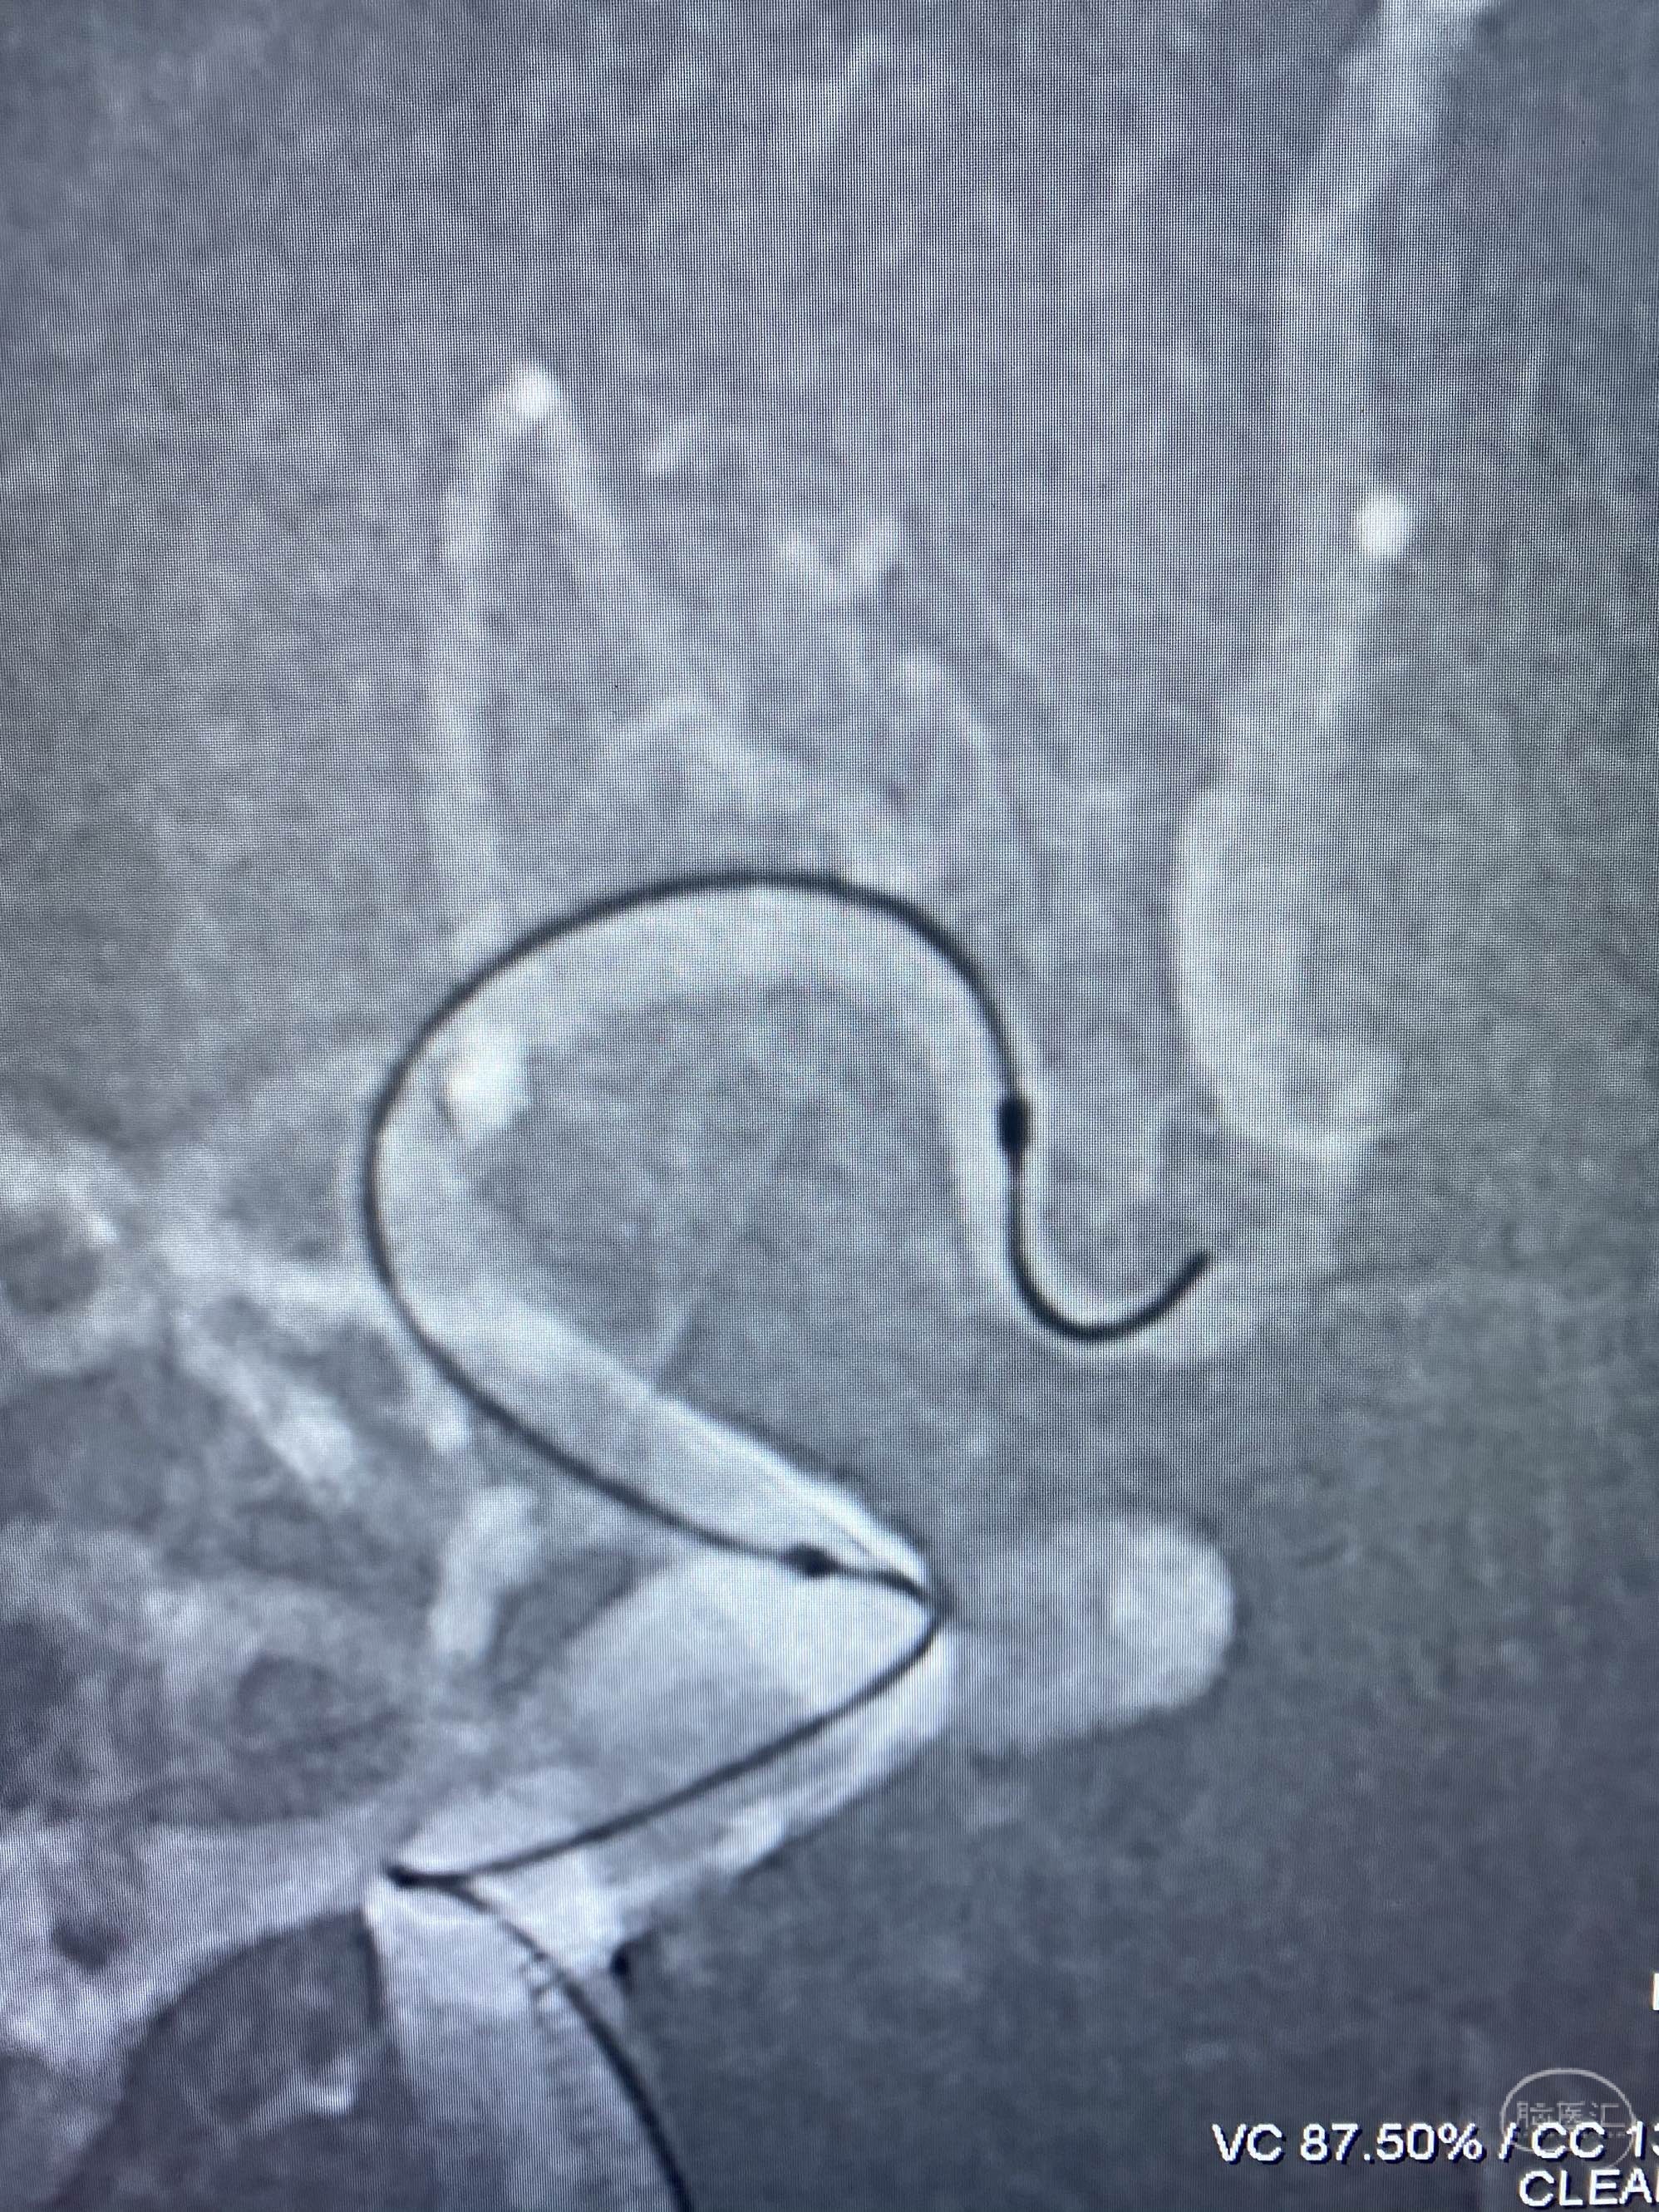

MLS,M79Y,sah,双侧MCA烟雾病,Heubner返动脉瘤,前交通段开窗,细支发出Heubner返动脉,瘤颈细长,瘤颈口比微导管细,弹簧圈2mmx3cm“隔山打牛”填塞治愈,Heubner返动脉保留。